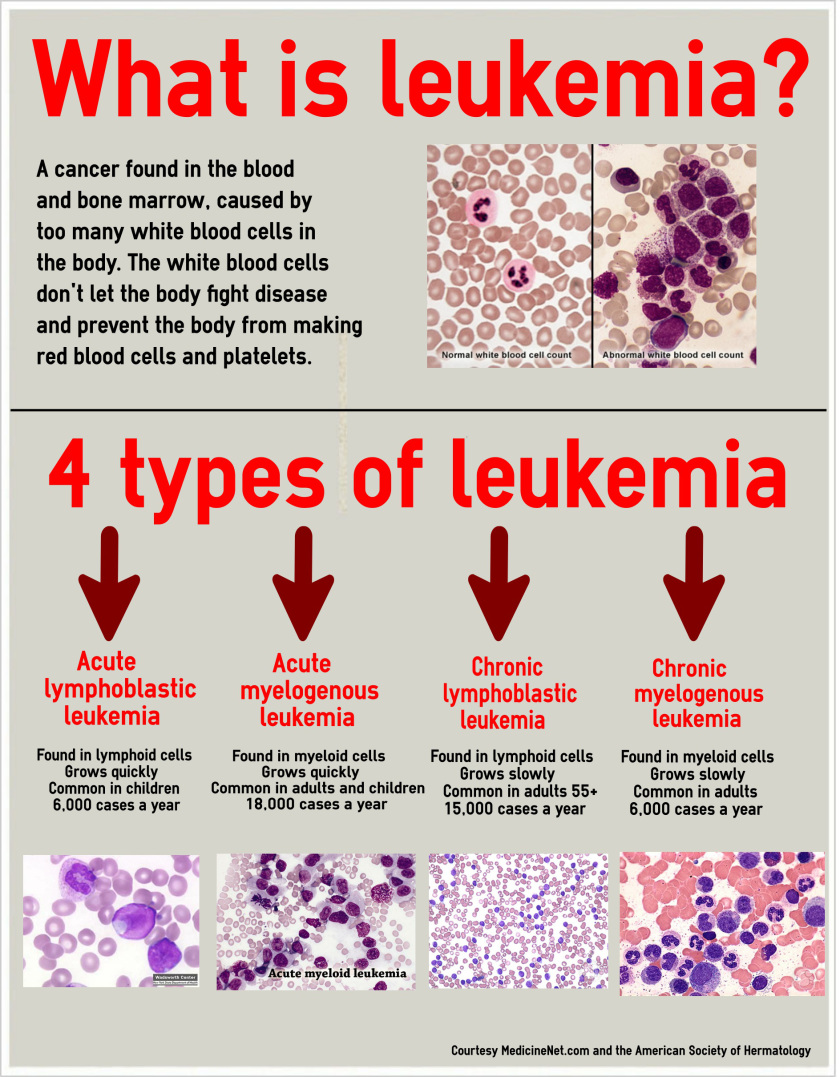

- Blood defects and diseases (e.g. leukemia, sickle cell anaemia etc.)